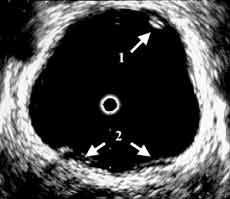

Рис. 2 и 3. Цистэндосонограммы. (Слева) Рак мочевого пузыря стадия Та. 1 - опухоль, 2 - устья мочеточников.